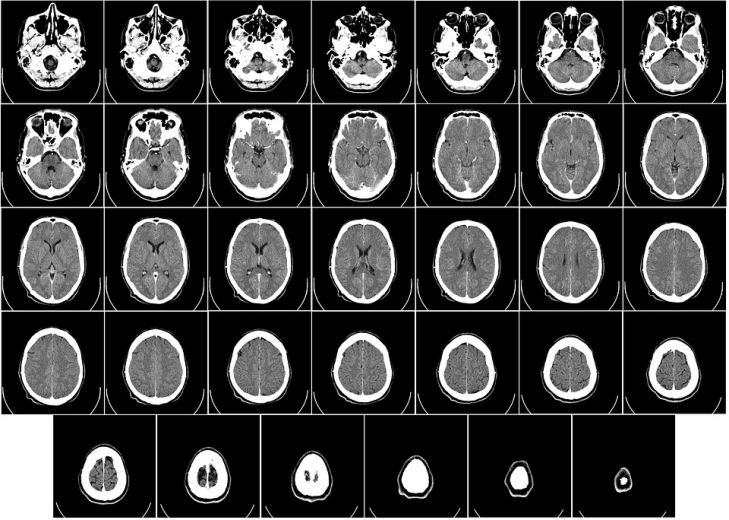

К такому выводу специалисты пришли в результате изучения результатов посмертного сканирования повреждённого мозга.

Магнитно-резонансная томография высокого разрешения показала наличие физических следов в мозге, которые учёные назвали «чёрными пятнами». В зоне повреждения были обнаружены железно-маркированные клетки крови, доказывающие наличие разрывов сосудов и микрокровоизлияний.